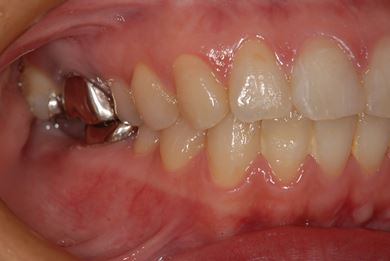

| 性別/年齢 | 女性 / 39歳 | ||||||||||||||||||||||||||||||||

| 主訴 | 右奥歯の虫歯と、右奥のインプラント治療について相談。 | ||||||||||||||||||||||||||||||||

| 治療方針 | 右下奥欠損部分をインプラント治療にて、機能的・審美的回復を行う。 | ||||||||||||||||||||||||||||||||

| 治療内容 | インプラント1本、ハイブリッドセラミッククラウン1本 | ||||||||||||||||||||||||||||||||

| 総治療費 | 329,963円 | ||||||||||||||||||||||||||||||||

| 治療期間 | 5ヶ月 |